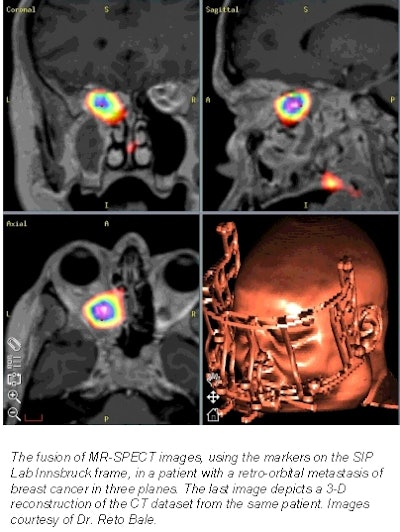

In the first study Bale presented, SPECT and PET images were fused with MRI and CT images in order to combine functional and anatomical information. CT (LightSpeed Plus, GE Medical Systems, Waukesha, WI) and MRI (Magnetom Sonata 1.5 tesla, Siemens Medical Solutions, Iselin, NJ) datasets of 13 patients were superimposed with SPECT images (Vertex V60, ADAC Laboratories, Milpitas, CA) to the desired extent in the axial, coronal, and sagittal planes using a pair-point matching algorithm.

The CT and MR images were fused with a root-mean-square (RMS) error value of 0.8 mm. The CT and SPECT images were fused with an RMS of 2.3 mm. Fusion took anywhere from 5-10 minutes for each data pair. The successful fusing of functional and anatomical images gave the neurosurgeons important information about tumor response and activity, Bale concluded.